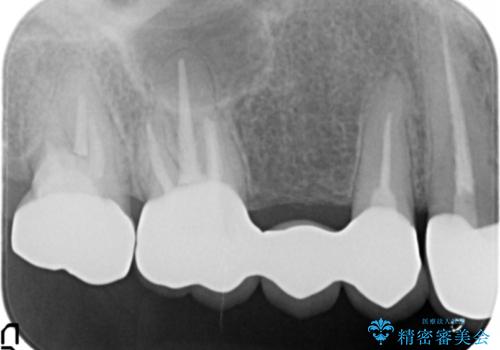

患者様のご希望により、金属を使わないオールセラミックのブリッジによる補綴治療を行いました。

金属の土台も除去し、ファイバーコア(金属を使わない強度のあるしなやかな土台)へやりかえました。

- ¥407,000 (仮歯・クラウン×3本、土台×2本) ※税込費用は治療当時の料金となります

自然な仕上がりと咬み心地に喜んで頂けました。

クラウンの種類:オールセラミッククラウン スタンダード